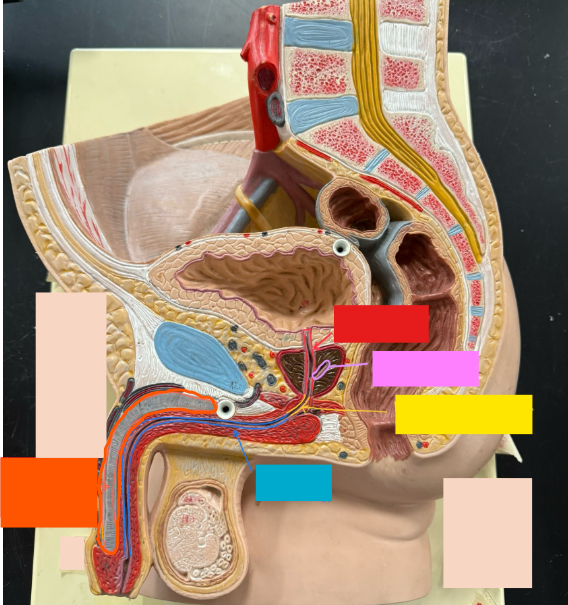

What is the name of the red box?

Ureter

What is the name of the purple box?

Rectum

What is the name of the yellow box?

Anus

What is the name of the red box?

Scrotum

What is the name of the orange box?

Corpus cavernosum

What is the name of the light blue box?

Spongy urethra

What is the name of the red box?

Prostatic urethra

What is the name of the pink box?

Ejaculatory duct

What is the name of the yellow box?

Membranous urethra